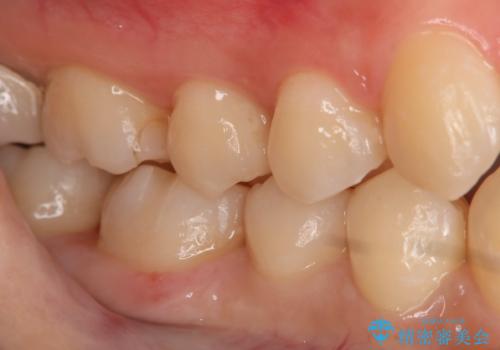

- 右下大臼歯の保険材料劣化に伴う虫歯の治療を希望された患者さまです。

審美性や精度の高い治療を希望されたので切削量や形態を考慮し、セラミックインレーでの治療を選択しました。

保険治療で使用される材料は劣化しやすく直下で虫歯が進行していることが多いです。

今回の患者さまは遠心部の虫歯が深かったのでCRで裏層した上で形成・印象を行いインレーセットを行っています。